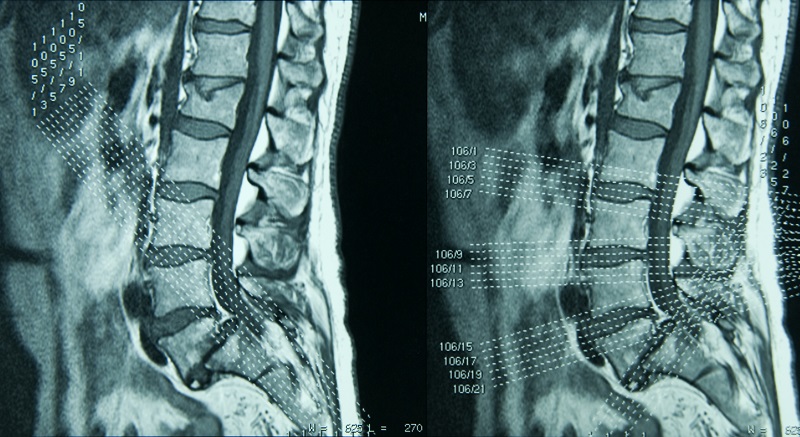

Lumbar Spine MRI is one of the most frequently ordered advanced imaging studies in Medicare populations and consistently one of the most denied. High utilization combined with heightened Medicare scrutiny makes this service line a key area of financial and compliance risk for providers and healthcare organizations.

Lumbar Spine MRI demonstrates a familiar pattern: high order volume, high audit visibility, and high denial rates driven primarily by documentation gaps, not inappropriate care.